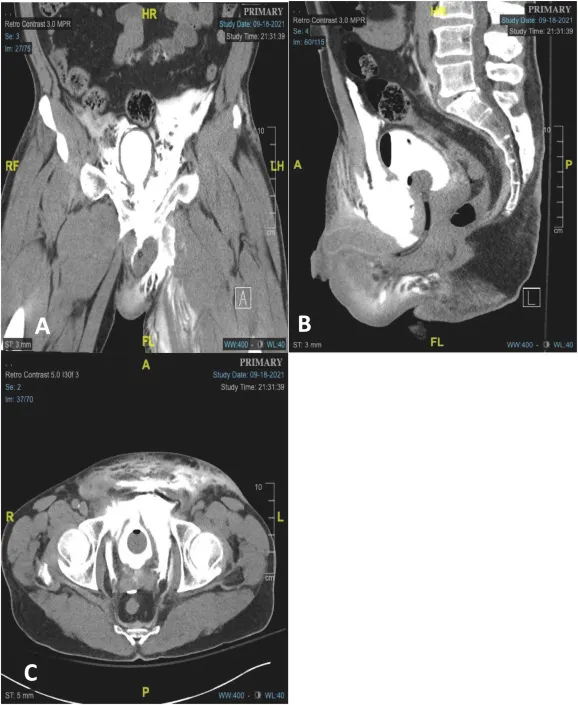

Bladder Injury:

- Assoc. w/ pelvic fractures (~80%).

- Types: Contusion, Extraperitoneal (EPR), Intraperitoneal (IPR).

- Sx: Gross hematuria, suprapubic pain, inability to void.

- EPR: Localized signs.

- IPR: Peritonitis.

- Dx: Retrograde cystography / CT cystography.

- EPR: "Molar tooth" sign (extravasation).

- IPR: Contrast around bowel.

⭐ Pelvic fracture with gross hematuria strongly suggests bladder injury; cystography is key.

- Mx:

- Contusion/EPR (uncomplicated): Catheter drainage (7-14 days).

- IPR/EPR (complicated): Surgical repair.